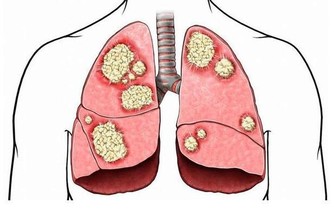

毒素不清,會累積成癌 在大腸癌的發生部位和發生機率中,直腸和乙狀結腸得癌症的機率最高,幾乎有百分之七十的腸癌都集中從肛門上來六十公分的這一段,因為這裡是宿便最容易囤積的地方,毒素都累積在這裡,這段腸子就像家裡的垃圾桶,等到垃圾積滿了才會去倒。咖啡灌腸最主要就是針對這一段腸道進行清腸排毒。

腸癌目前高居國人癌症發生人數的第一名,是有跡可循的,證明現代人飲食中的毒素真的太嚴重,加上排泄不良,宿便的毒素都累積在大腸內。